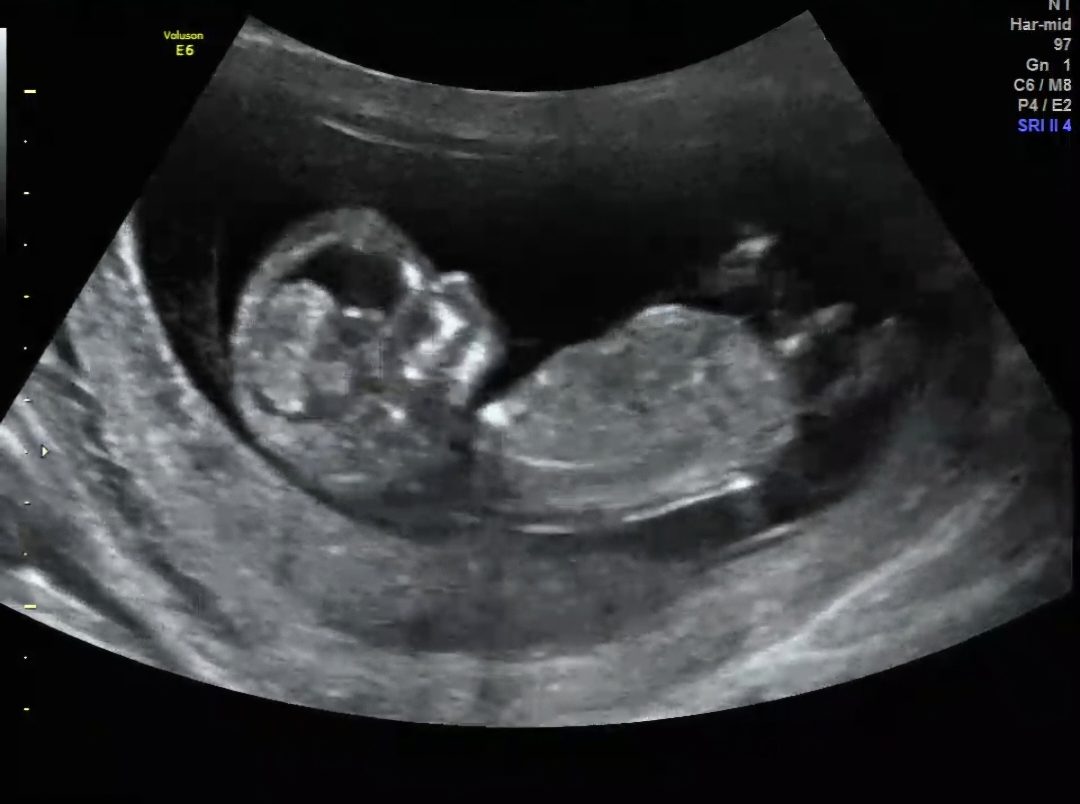

성별 예측해주세요🫶

12주긴 하지만, 혹시 성별이 보이실까요??